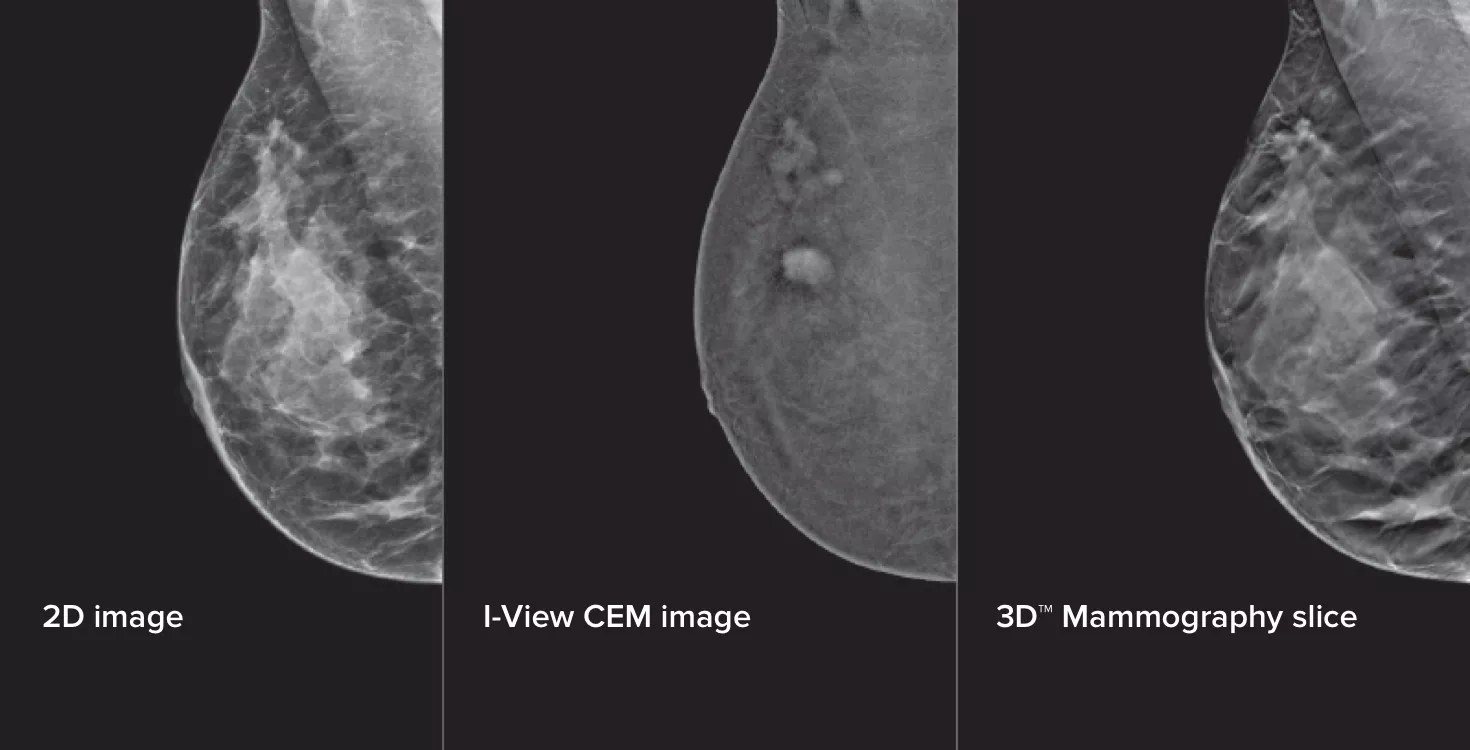

Contrastversterkte mammografie (Contrast Enhanced Mammography; CEM), het in beeld brengen van de borst met gebruik van jodiumhoudend contrastmiddel om gebieden met een verhoogde bloedtoevoer in de borst zichtbaar te maken, kan helpen om het beeld van verdachte laesies te versterken. De I-View-software kan de kracht van CEM combineren met 2D- en tomosynthesebeelden, allemaal bij één compressie, voor anatomische en functionele beeldvorming in één onderzoek.1

Deze software legt zowel anatomische als functionele informatie vast bij één onderzoek door gebruik te maken van ons vermogen om 2D-, contrast- en tomosynthesebeelden te produceren bij slechts één compressie.1